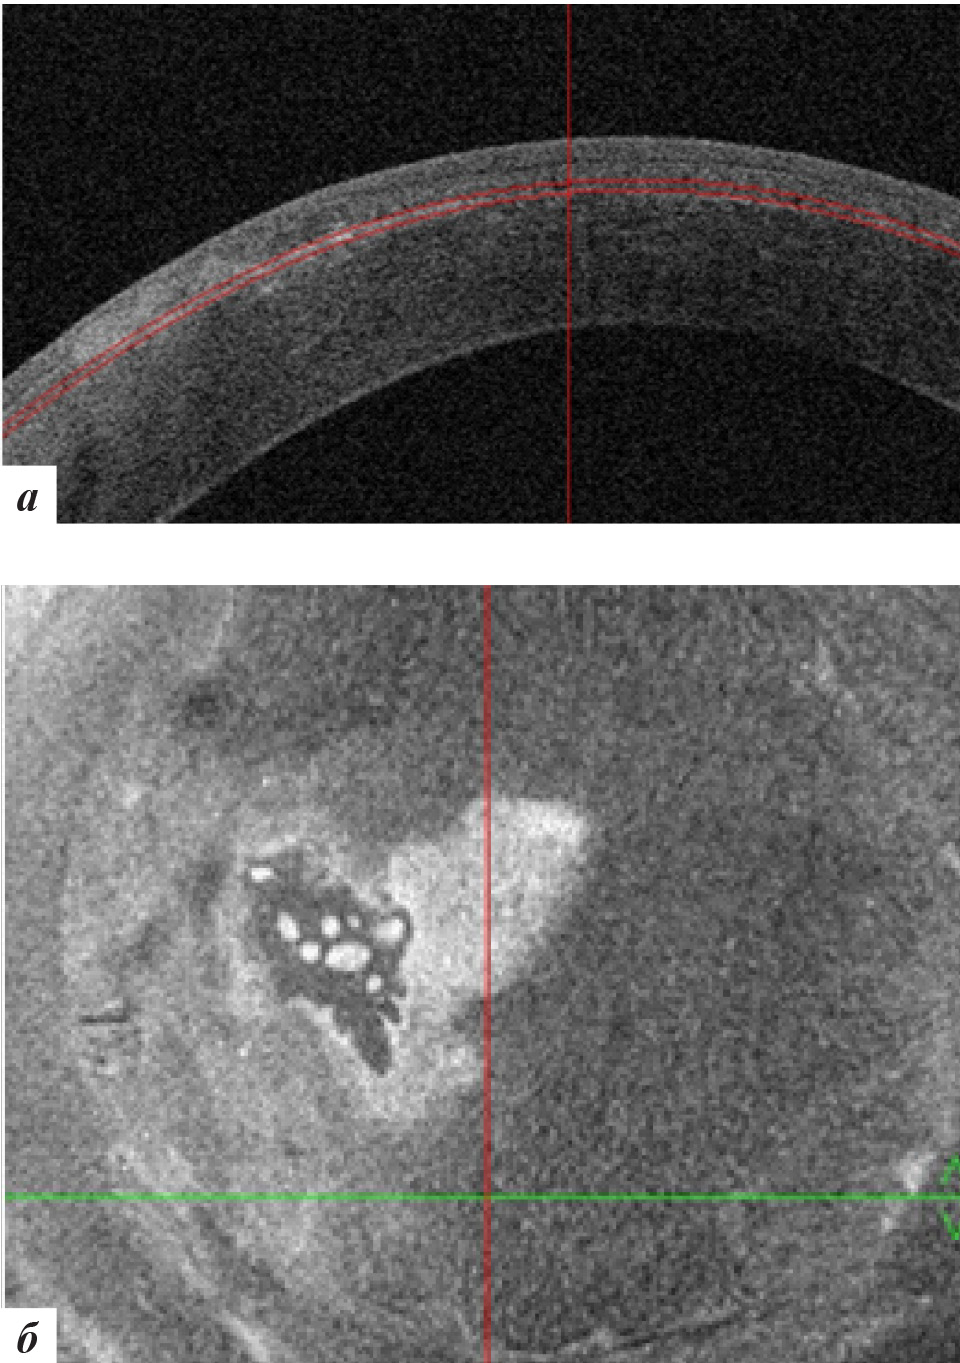

Рис. 2. Данные ОКТ роговицы правого глаза: а – горизонтальная проекция; б – фронтальная проекция

Рис. 4. Данные ОКТ роговицы левого глаза: а – горизонтальная проекция, б – фронтальная проекция